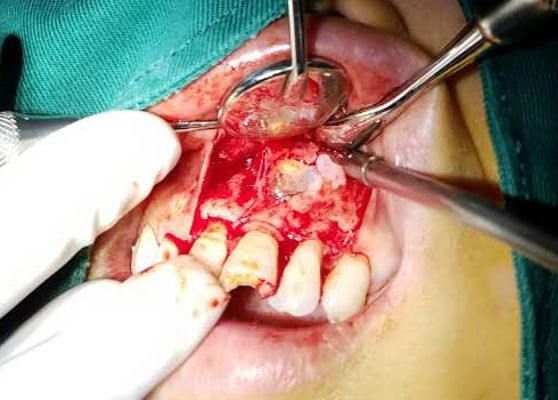

趙幫樹病例

來源于江思玉2群收集整理